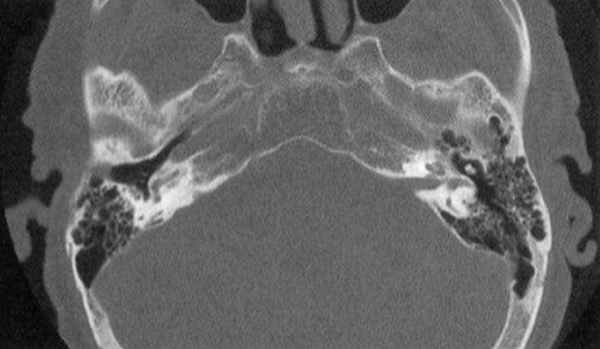

Остеодистрофия височной кости на томограмме

в) Фиброзная дисплазия на компьютерной томограмме. Фиброзная дисплазия представляет собой аномальную пролиферацию фиброзной ткани с костными трабекулами в медуллярной полости, ведущую к повышению плотности и утолщению пораженной области. Процесс обычно односторонний, что ведет к асимметрии. В височной кости чешуя становится толстой, пневматические пространства облитерируются. Наружный слуховой проход суживается новообразованной костной тканью.

По мере уплотнения плотности пирамиды выраженность лабиринтной капсулы снижается, сливаясь с костными тканями. Дальнейшее прогрессирование ведет к сужению внутреннего слухового прохода и облитерации пространства лабиринта.

Фиброзная дисплазия: А. Аксиальная, Б. Коронарная КТ.

Диффузное утолщение и склероз височной кости, сужение наружного и внутреннего слуховых проходов.